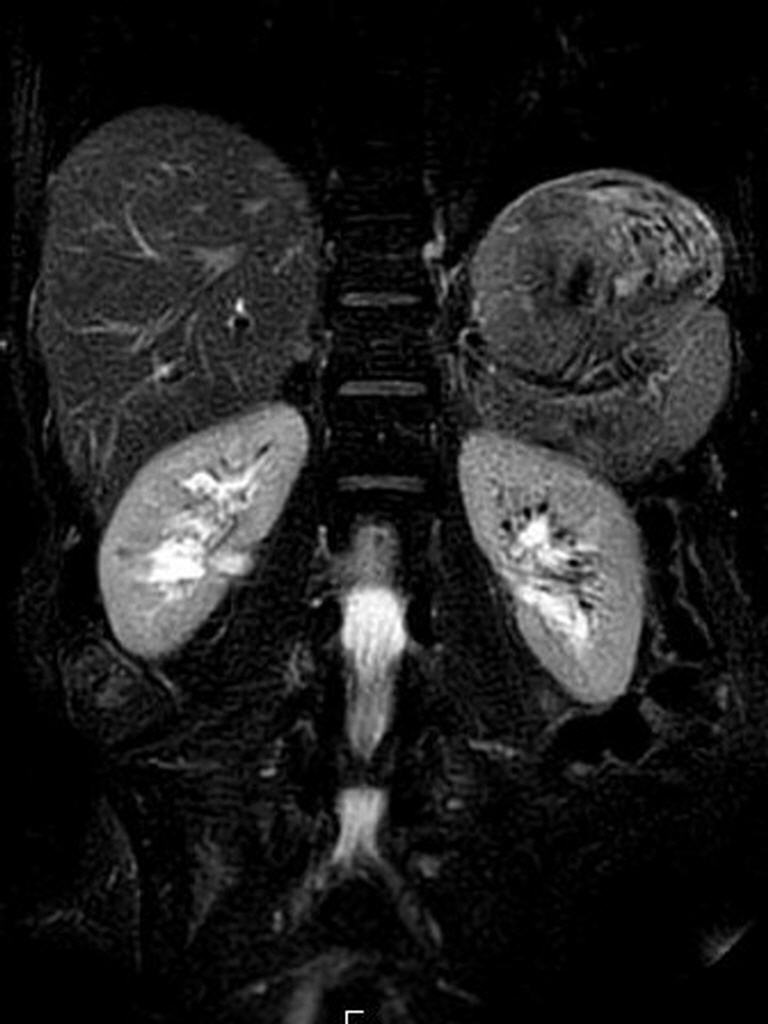

- Diagnostik der Oberbauchorgane